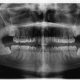

Cualquier problema bucodental tienen una incidencia muy negativa en el rendimiento deportivo; un dolor de dientes, sin más, puede limitar a una persona, incluso incapacitarla, para realizar su entrenamiento o una competición. Cuando se tiene una mala salud dental y periodontal, la situación puede ser aún peor. Padecer una infección o inflamación puede causar problemas en otras zonas del organismo. No debe olvidarse que las bacterias que se encuentran en estas infecciones guardan relación con problemas a nivel respiratorio, muscular, cardiovascular y/o articular y diabetes. Son cada vez más los estudios que demuestran esta relación, que provoca problemas en el rendimiento deportivo. Si faltan piezas dentales, estas están mal alineadas, o existe un mal engranaje entre la arcada superior y la inferior, también pueden surgir problemas en el entrenamiento. Es más, masticar incorrectamente es la causante del 30% de los dolores de cuello y espalda, y tiene una relación directa con problemas relacionados con el equilibrio.